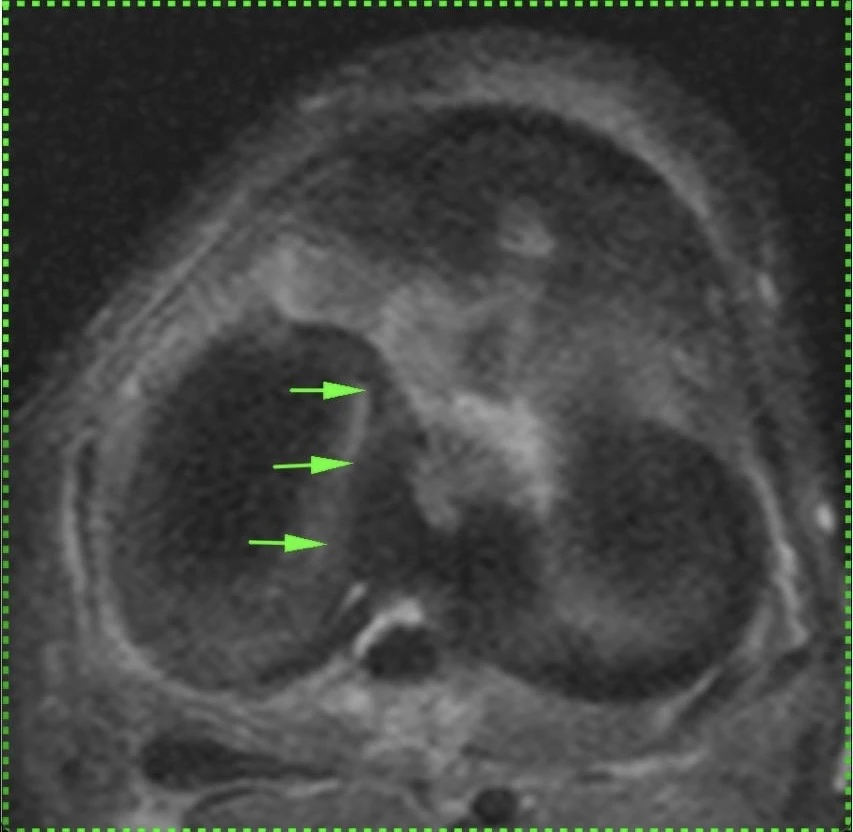

Обширная, ветвистая венозная мальформация (ранее известная, да и до сих пор тоже, как гемангиома) мягких тканей области коленного сустава.

Картина типичная, дифференциальная диагностика не требуется.

Представляет собой скопление аномальных, расширенных, извитых венозных сосудов, стенка которых гистологически не отличается от стенок обычных вен. Хорошо видны связи мальформации с обычными венами. Внутри некоторых из полостей видны выпадение сигнала, которые являются флеболитами (кальцинированными внутрисосудистыми тромбами).

Кстати, может никак не проявляться клинически, будучи даже таких больших размеров.